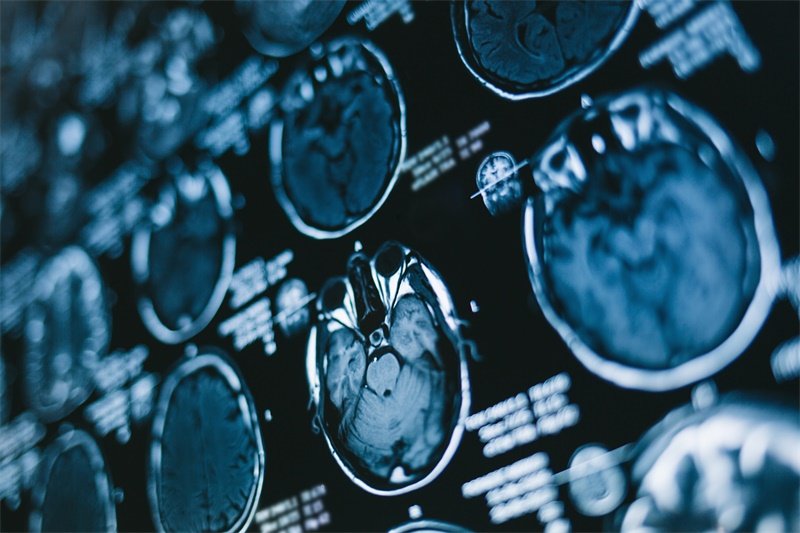

在进行脑动静脉畸形切除术前,患者首先需要接受全面评估。这包括影像学检查,如脑部MRI或CT扫描,以详细了解畸形的结构和其对周围脑组织的影响。了解异常血管的形态和位置对于手术计划至关重要。